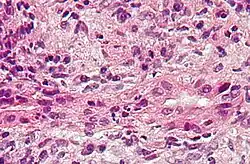

Obraz histologiczny

- faza I – uszkodzenie dróg żółciowych; naciek zapalny z komórek jednojądrzastych; nieliczne granulocyty w przestrzeniach wrotnych

- faza II i III – reakcja przewodzikowa; nacieki zapalne w przestrzeniach okołowrotnych; żółciowa martwica kęsowa; zanik przewodzików żółciowych; włóknienie

- faza IV – dokonana marskość wątroby; makroskopowo wątroba jest ciemnozielona.